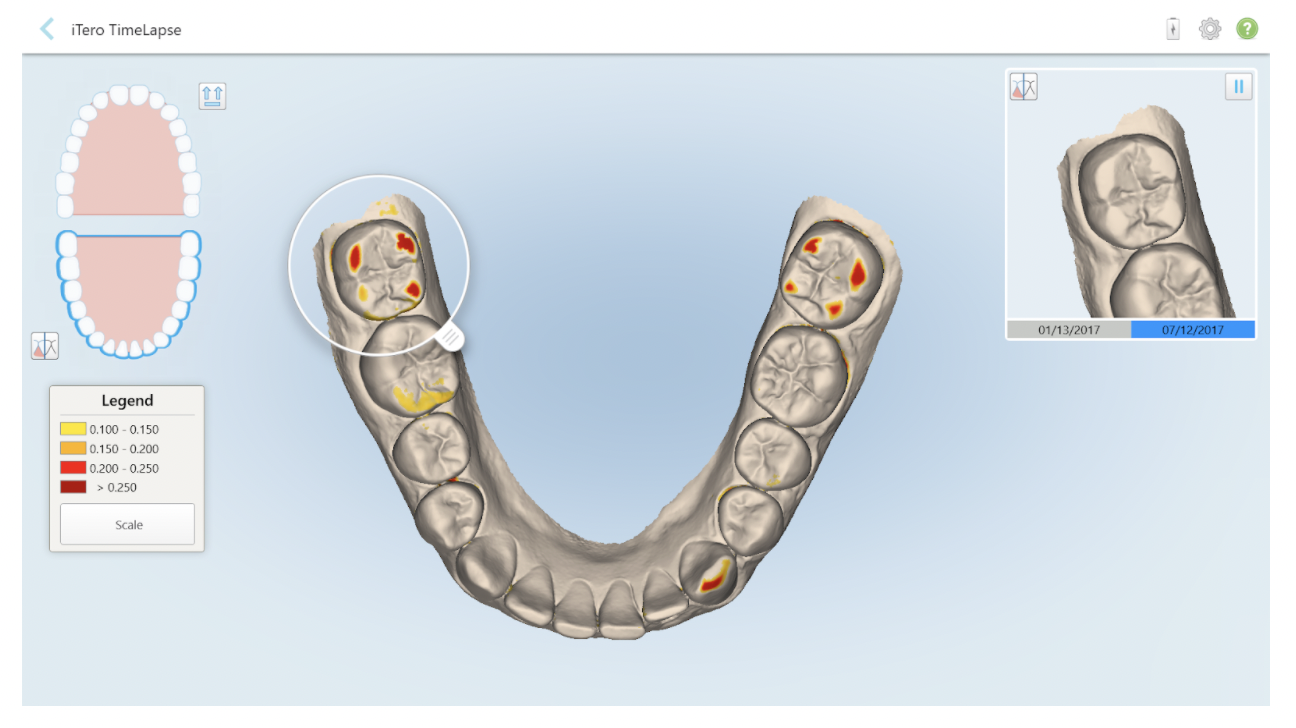

3) It can forecast problems with the TimeLapse feature

This innovative feature enables us to forecast issues and diagnose problems by comparing different scans with its innovative TimeLapse feature.

This can give us a better understanding of the way in which the soft tissue is receding, as well as any abrasion, erosion and tooth movement. By comparing scans from previous appointments, we can easily see changes and treat them appropriately.